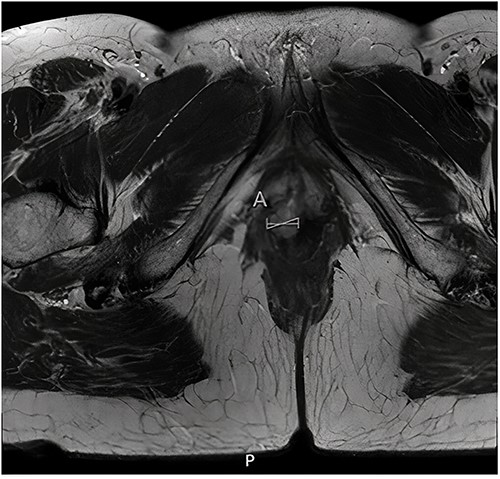

Histopathological examination of the biopsy showed an adenocarcinoma metastasis of rectal origin. A full body positron emission tomography (PET)-scan and MRI were made and confirmed the vaginal lesion of 1.7 × 1.4 × 1.5 cm located in the posterior wall of the vagina just above the puborectal sling (see Figs 1 and 2). From the histopathological and imaging diagnostics we concluded that the patient had a distal rectovaginal septum metastasis of rectal origin.

Axial view of diagnostic MRI-rectum with the solid tumour indicated with the linear mark ‘A’.